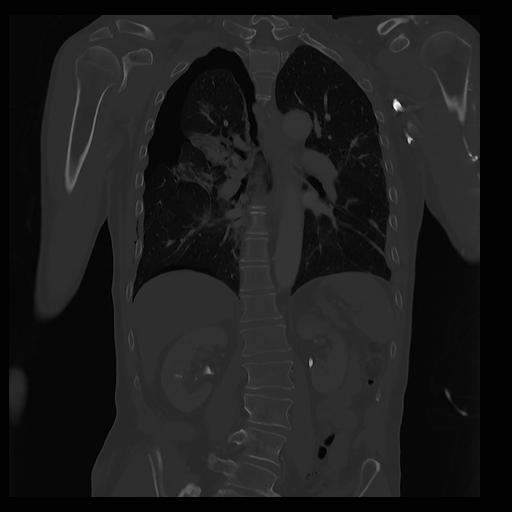

32 PULMON,CE,Coronal,3.000,PULMON,Coronal,